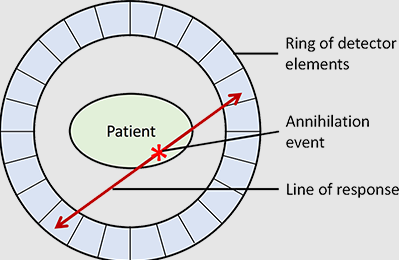

What is the relationship between each detector pair inside the ring of detectors in a PET camera?

Each detector works together with the detector opposite to it – allows it to pick up on a line of response

What is a line of response?

When the photons from an annihilation reaction are emitted, they will travel in opposite directions of one another – makes a 180-degree line almost

How does a ‘dot’ from our image translate from the reaction at the PET detectors?

The detectors create a dot on our scanned image from the point at which the 2 photons are overlapping – or where they cross each other in the ring of detectors but we still need more information to specifically determine it!

What is needed in order for the PET detectors to determine where an annihilation reaction occurred on a line of response?

Requires multiple line of responses to figure out where the intersection of where the annihilation reaction took place

Is a line of response able to determine where the photon originated from?

No, it’s only able to determine where the annihilation took place